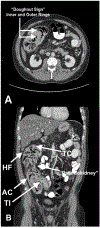

Case summary: A 33-year-old Caucasian male with cystic fibrosis presented with an acute abdomen diagnosed via imaging as colocolonic intussusception. He was managed with fluid replacement therapy and polyethylene glycol. He was re-admitted due to recurrence likely secondary to recurrent constipation and development of a fecalith. Surgery was contraindicated due to absence of tissue ischemia or necrosis.

Discussion: Several possible etiological factors have been described, especially some that tend to occur within the context of CF disease, such as DIOS and PERT, and symptoms of colocolonic intussusception are similar to those of other causes of an acute abdomen but distinguishable by advanced imaging modalities. Due to risk of recurrence, an etiology of intussusception should be sought.